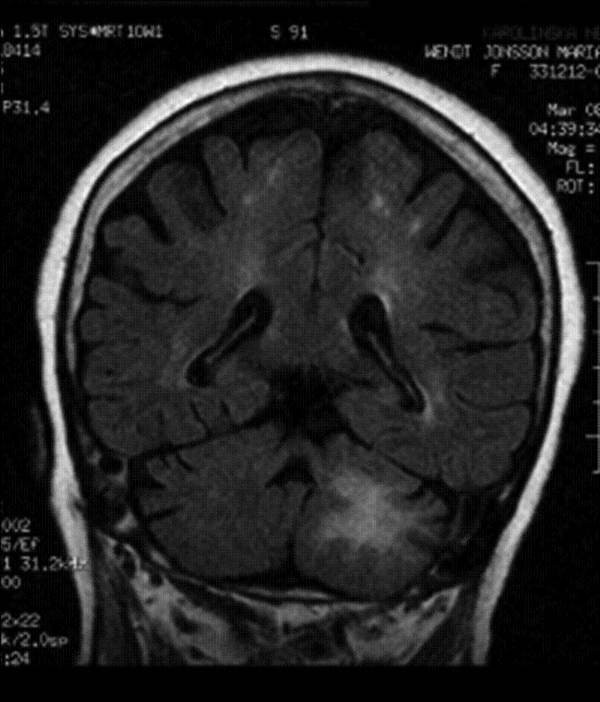

3. Bệnh chất trắng đa ổ tiến triển (PML)

Căn bệnh kỳ lạ này được miêu tả như một chứng rối loạn thần kinh. Chứng bệnh (Progressive Multifocal Leukoencephalopathy - PML) này được đặc trưng bởi sự phá hủy các tế bào sản xuất myelin.

Myelin là một chất dạng dầu có tác dụng bảo vệ hệ thần kinh trong não và tủy sống con người hay còn được gọi là chất trắng của hệ thống thần kinh trung ương.

Bằng cách này, căn bệnh phá hủy dần lớp màng bảo vệ các dây thần kinh trong não bộ. Nó gây ra sự suy giảm hoạt động não, biểu hiện là chân tay yếu khó cử động, mất trí nhớ, mất ngôn ngữ... và có thể dẫn đến cái chết. Căn bệnh này bị gây ra bởi một loại virus có tên JC.

Tuy nhiên virus JC chỉ gây bệnh khi hệ miễn dịch bị suy yếu nghiêm trọng chẳng hạn như ở người nhiễm HIV/AIDS, có khối u ác tính huyết học hay ở người được ghép nội tạng buộc phải sử dụng thuốc ức chế miễn dịch. Nhìn chung tỉ lệ mắc bệnh PML là khoảng 1/200.000 người.

PML phá hủy dần não bộ.

Căn bệnh này vẫn là đề tài nghiên cứu đau đầu của các nhà khoa học bởi hiện nay, các chuyên gia vẫn chưa có biện pháp nào để phòng ngừa hay tiêu diệt loại virus này, tránh không cho nó phát bệnh.